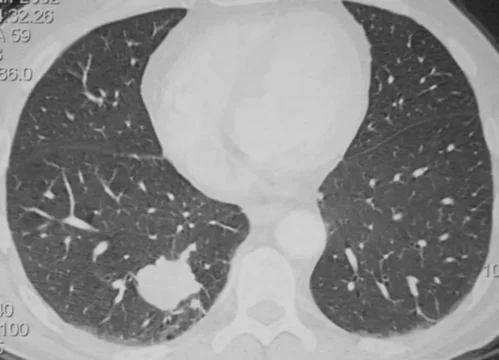

Cancérologie thoracique

Pathologies

Cancers du poumon, de la plèvre et du médiastin